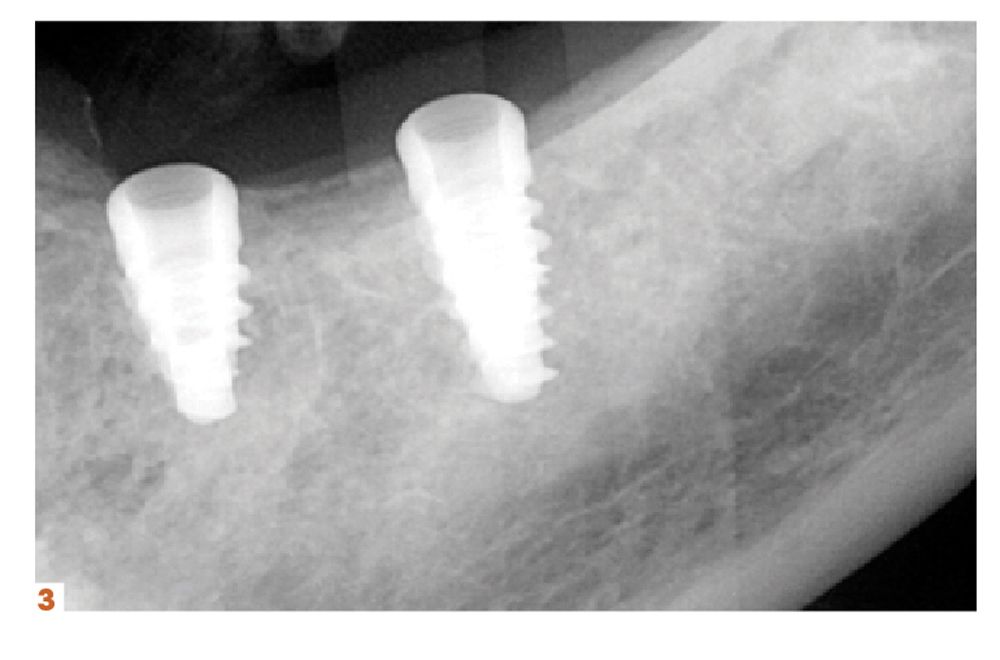

Another area of growth for practices can come from providing more implant services.

“Twenty-two years into my career, I didn’t realize how big of a game changer implant placement would be for my practice. Now that we can tell patients that we can handle it here in the practice, most patients are eager to move forward with treatment,” says John R. Nosti, DMD. “It’s, ‘Oh, you can do this now? That’s great!’

“So being able to offer that service to my patients, who trust me and know that I’m capable of providing them the care or I wouldn’t offer it to them, has been great for them as well as my practice. It’s convinced a lot of patients who’ve been on the fence, even though they wanted the implant, into accepting treatment. And then there’s new patients I’m meeting who have been to my website or seen the marketing pieces we’ve put out. They’ve seen the smiles we create and the testimonials, and they come to the practice because it’s all done in my office.”

There are a few products, and courses, in particular that Dr Nosti counts on to help with his growth.

“I strongly recommend that anyone who’s interested in placing implants take the Misch-Resnik Implant Institute continuum. Just in the first session alone, you learn enough about extracting and grafting to bring that back to your practice and add it to the services you offer,” he says. “Being able to perform predictable bone grafting procedures for your patients can add enough revenue to your practice to pay for the entire continuum. And that’s before implant placement even enters the picture.”

He adds, “Doctors really owe it to themselves to look into implants and have that be a part of their practice. Their patients will be able to chew food easier, smile with more confidence, and enjoy all of the life improvements that implants bring. And that’s amazing because, don’t we all want to better our patients’ lives?”

Figures 1-4.For his first implant surgery, which was completed at the time he was attending courses at the Misch-Resnik Implant Institute continuum, John Nosti , DMD, placed 5 Hahn™ Tapered Implants in the posterior mandible for a patient who was especially eager to have him complete the entire process, from implant placement to the final screw-retained restorations. Glidewell offers a complete solution for implant and restorative cases. This solution is designed to provide the best care for patients and the greatest efficiency in terms of clinical workflows. The company’s new lifetime warranty stands as a commitment to the quality of the company’s implants and restorations and reflects the solid research and development and clinical validation dedicated to earning the trust of the dentists that Glidewell serves.